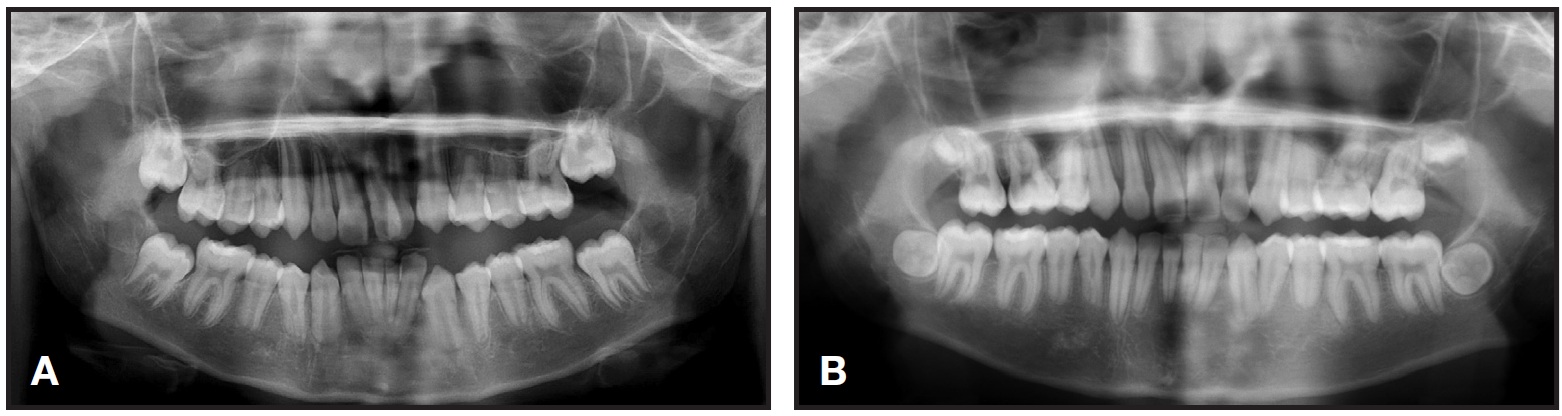

Cephalometric analysis indicated a Class II skeletal base and a convex profile due to a prognathic maxilla. The upper incisors were proclined, and both lips were protruded in relation to the E-line (Table 1). The panoramic radiograph revealed generalized short roots, impacted lower third molars, and a missing upper right third molar.

The root/crown ratios for the first molars, premolars, canines, and upper incisors were calculated as proposed by Lind.1 The most affected teeth were the upper right and left central incisors, with root/crown ratios of .85 and .90, respectively (Table 2).

The patient and his mother reported that no other family members had been diagnosed with short roots. Two brothers of the patient had been previously treated in our clinic and did not present with generalized SRA, but one displayed mild shortening of the premolars—a condition that worsened slightly during orthodontic treatment (Fig. 2).

Fig. 2 Patient’s brother before (A) and after (B) orthodontic treatment.

The upper incisors were substantially retracted, and the lower incisor inclination was reduced. There was improvement in the lip projection, especially the lower, in relation to the E-line (Table 1). The length of the roots—including those of the canines, which underwent active retraction for about 20 months—was basically unchanged from the initial radiograph (Table 2). Because the lower third molars showed significant mesial angulation, they were recommended for removal, along with the unopposed upper left third molar.